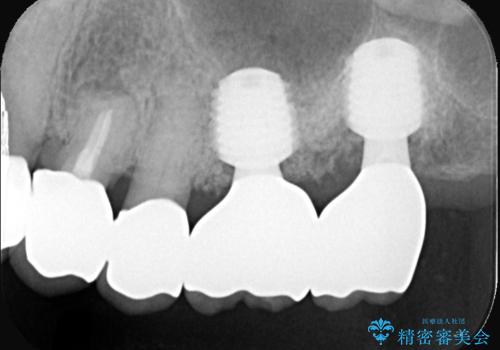

難症例の奥歯も3ヶ月で機能回復!抜歯即時インプラントでスピード解決